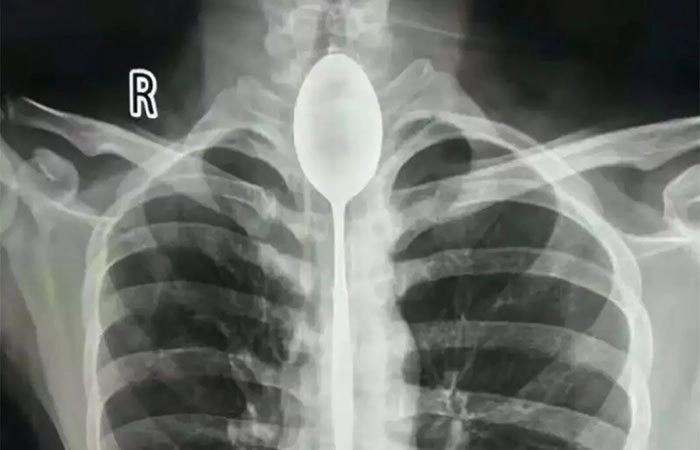

Снимок человека, у которого в пищеводе застряла стальная ложка